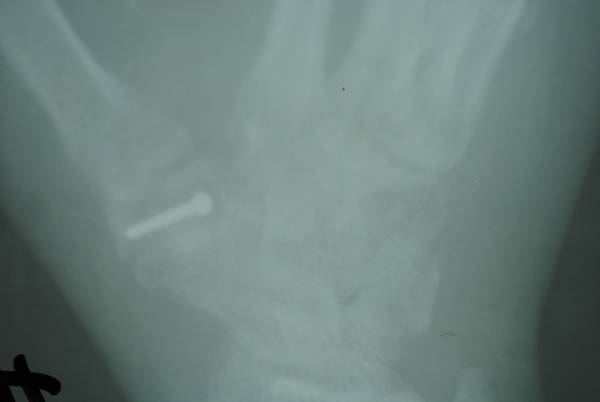

混凝土高压灌注伤

CIMG3502.JPG 片子忘法拉相机不好!@ CIMG3500.JPG

术后15日,皮瓣成活,复查x片豌豆骨游离移植修复大多角骨大部缺损位置良好。